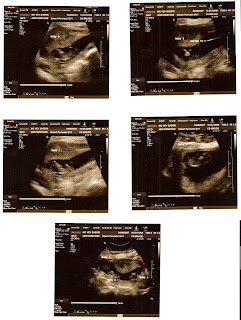

This is the end of the our road with Nevada Fertility Cares (NFC). Dr. Littman who helped us initially who left on maternity leave saw us for our last appointment. There was some inkling that maybe we could see boy parts, but no firm confirmation….Wayyyy too early. Babies look great, growing well.